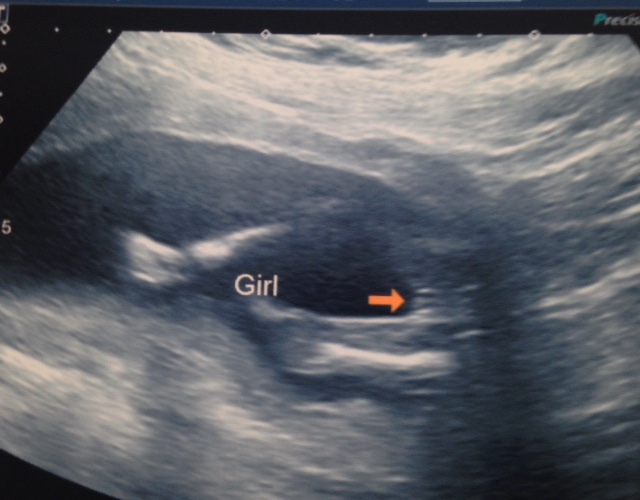

Just wondering if anyone has a guess on my scan pics, the technician made me feel stupid when I asked her about the nub theory and if she was familiar with it, so I didn't ask for a clear shot. I cant make anything out..

Thankyou in advance